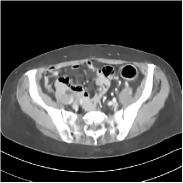

IV-F2 SUPER with Data-fidelity only cost

To further explore the different special cases of SUPER, here we empirically validate the relative effect of the data-fidelity term used in (P0) by setting β=μ=0𝛽𝜇0\beta=\mu=0. In particular, at reconstruction time, the initial FBP image is passed through networks learned in a supervised manner, each time followed by few iterations of descent on the data-fidelity cost, which enforces data consistency in conjunction with the supervised learning-based network.

Figure 5: Reconstructed images of slice 150 of patient L192 using of FBP, PWLS-ULTRA, FBPConvNet, SUPER-FCN-DataTerm, and SUPER-FCN-ULTRA, respectively, shown along with the reference.

Fig. 5 shows reconstructions using FBPConvNet, SUPER-FCN-DataTerm (i.e., β=μ=0𝛽𝜇0\beta=\mu=0), PWLS-ULTRA, and SUPER-FCN-ULTRA, respectively. For SUPER-FCN-DataTerm, when optimizing the data-fidelity term, we start with the deep network’s output and ran 5 iterations for the data-fidelity term to avoid overfitting to the analytical FBP images. In Fig. 5, obviously, FBPConvNet significantly suppresses noise and artifacts compared to PWLS-ULTRA, but it also over-smooths many details (e.g., features in the zoom-in box) in the reconstruction. SUPER-FCN-DataTerm, by enforcing data consistency, helps reduce overfitting issues and reconstructs image details and tissue boundaries better compared to the standalone FBPConvNet. Our SUPER-FCN-ULTRA method, however, exploits richer prior information (via the union of learned sparsifying transforms) and explicit network regularizer and outperforms the SUPER-FCN-DataTerm approach. Additional such comparisons for other selected test slices are included in the supplement (Fig. 15).